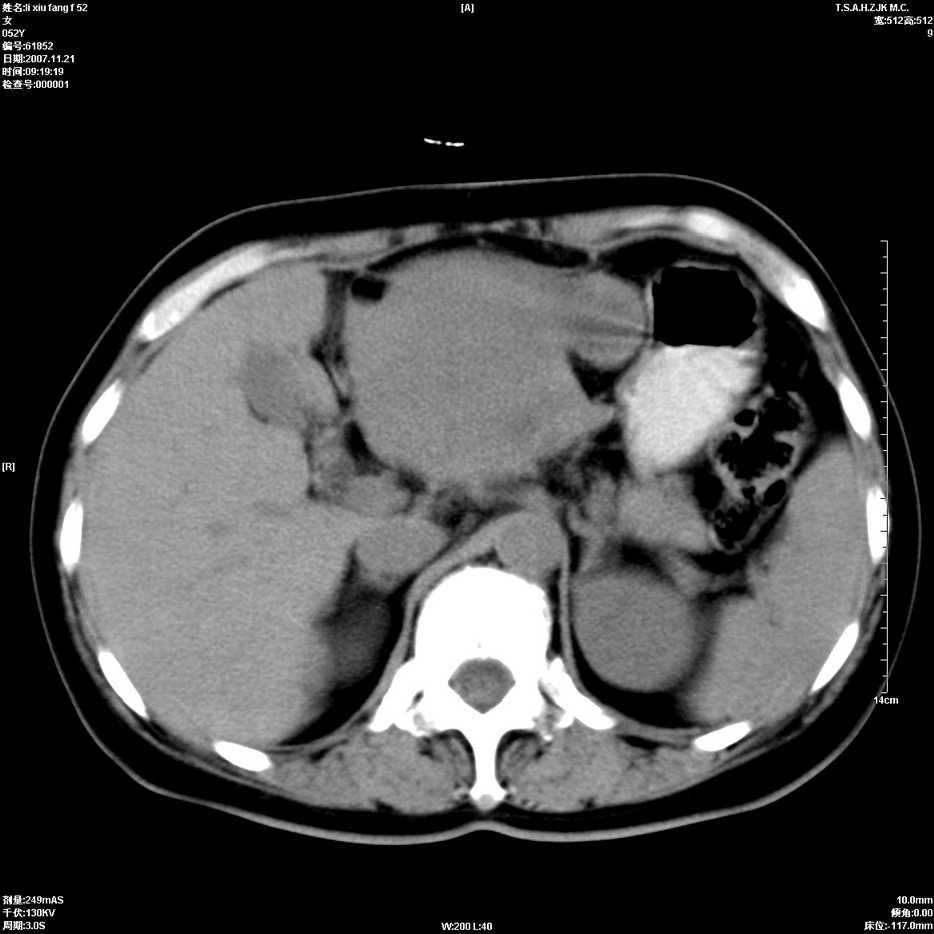

标题: CT12858:女,52岁,胎甲球蛋白861肝左叶占位,肝癌。下腔静 [打印本页]

标题: CT12858:女,52岁,胎甲球蛋白861肝左叶占位,肝癌。下腔静

肝左叶巨大低密度灶肿块,增强符合快进快出表现,有动静脉交通支;静脉期,下腔静脉内有充盈缺损,afp明显升高,支持肝癌并下腔静脉癌栓形成。

以下是引用拾荒者在2008-4-15 22:57:00的发言:[br]肝左叶巨大低密度灶肿块,增强符合快进快出表现,有动静脉交通支;静脉期,下腔静脉内有充盈缺损,afp明显升高,支持肝癌并下腔静脉癌栓形成。